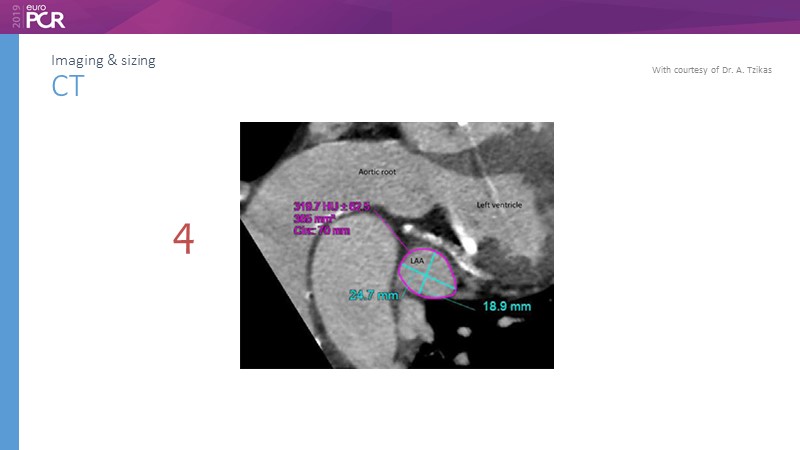

Pre-procedure planning

Previous Next